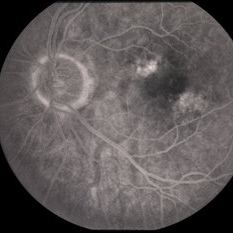

Age Related Macular Degeneration

Age Related Macular Degeneration

Mar 29 2013 by Henry J. Kaplan, MD

Geographic atrophy with small hemorrhages due to subretinal neovascular membrane development.

Condition/keywords: choroidal neovascularization (CNV), geographic atrophy